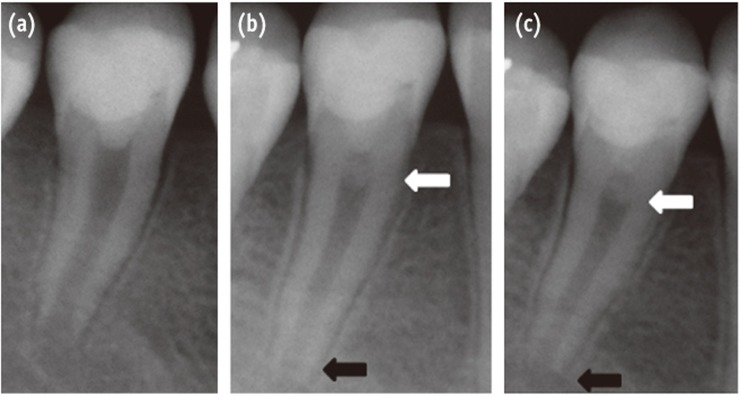

A 12 year-old girl presented at the emergency dental clinic, Hospices Civils de Lyon, Lyon, France, for an acute, spontaneous and lasting referred pain in the right posterior mandibular quadrant. Clinical and radiographic examinations revealed extensive occlusal caries invading the pulp on the second right lower premolar, an immature permanent tooth with incomplete root formation (Figure 1a). The diagnosis was acute pulpitis (#45).

After taking the informed consent of her parents due to the young age of the patient, a conservative pulpal treatment option was adopted in order to allow for further root formation and to preserve the growing potential of the root and the healing potential of the pulp. Accordingly, #45 was anesthetized by a peri-apical injection with 1.5 mL of a 2% articaine and 1/200,000 epinephrine solution (Primacaine Adrenaline 1/200,000, Acteon Pierre Rolland, Merignac, France) and isolated under rubber-dam.